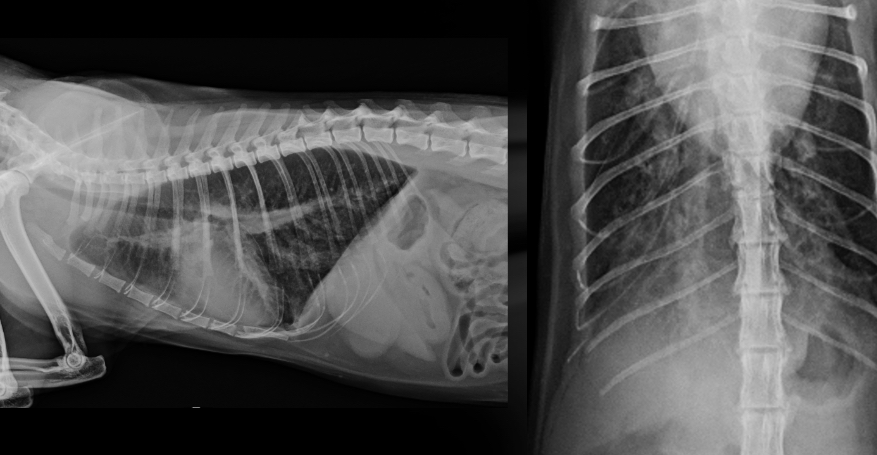

What part of the heart is enlarged

LAE